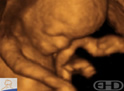

CinemaMovimentos Respiratórios |

Roteiro: यद्यपि गर्भाशय में कोई हवा नहीं होती, फिर भी भ्रूण 8वें सप्ताह से रुक-रुक कर सांस लेने जैसी गतिविधियां करता है। |